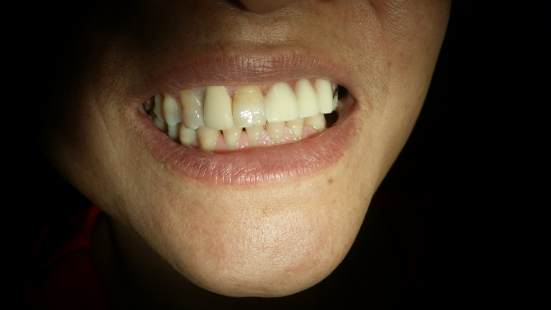

种植牙术后

种植牙术后 (2)